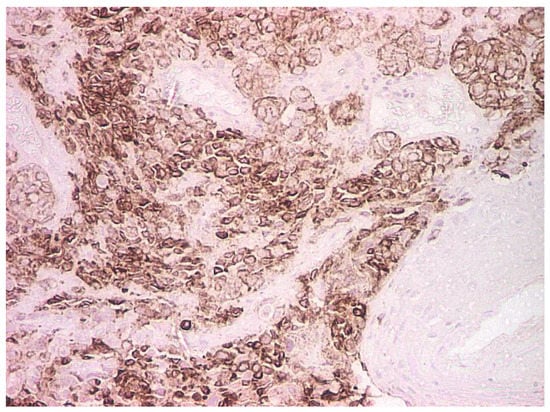

2. Case Report